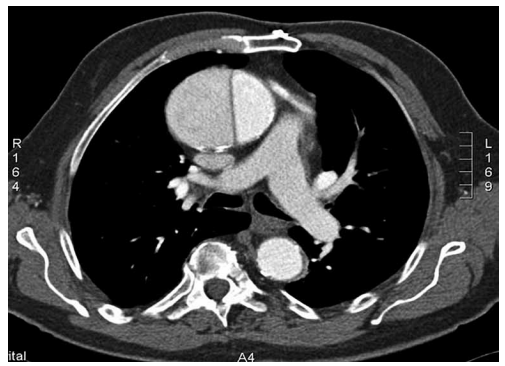

Realizou-se angiotomografia de tórax, conforme imagem a seguir

(Arquivo pessoal; imagem usada com autorização)